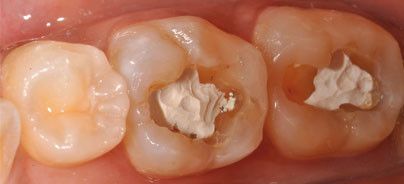

Eine 28-jährige Patientin wurde in unserer Praxis vorstellig, da sie mit ihren schnell schlechter werdenden Compositefüllungen in Zahn 36 und 37 unzufrieden war. Die klinische Untersuchung ergab Randverfärbungen und eine übermäßige Transparenz der bestehenden Füllungen (Abb. 1). Nach der Entfernung des Composites wurde klar, dass ein Zinkoxid-Eugenol-Zement als Unterfüllung verwendet worden war (Abb. 2). Damit kommen wir wieder auf die anfangs erwähnten grundlegenden Überzeugungen zurück. Diese Technik wird angewendet, um die Compositemenge bzw. Schichtdicke zu verringern und ein Bulk-Composite anwenden zu können, oder, wenn dies nicht gewünscht wird, zumindest den Schrumpfungsstress zu reduzieren. Zinkoxid-Eugenol-Zemente sind jedoch kein ideales Unterfüllungsmaterial, da Eugenol die Polymerisation negativ beeinflusst. Ein Kofferdam (OptraDam) wurde gelegt. Nach der vollständigen Kariesexkavation (Abb. 3a) wurden die Kavitätenränder mit einem 20-µm-Bohrer finiert (Abb. 3b). Ein selbstätzendes Bond wurde appliziert (Abb. 4), das Lösungsmittel verdampft und das Bond lichtgehärtet. Anschließend wurde ein fließfähiges Composite (Tetric EvoFlow) als erste Schicht eingebracht (Abb. 5). Dann erfolgte die Applikation von Tetric EvoCeram Bulk Fill in einem Schritt (Abb. 6). Das Material wurde an die Kavitätenwände in Richtung der Höckerabhänge adaptiert und 10 Sekunden lichtgehärtet (Abb. 7). In den Abbildungen 7 und 8 ist der Vorteil des Lichtleiters mit verkürztem Hals nach der Biegung deutlich erkennbar. Die Abbildungen 7a und 7b zeigen die von vielen Herstellern verwendeten konventionellen Lichtleiter; die neuen 10-mm-Lichtleiter der neuen, ergonomischen Bluephase Style von Ivoclar Vivadent sind in den Abbildungen 8a und 8b dargestellt. Zahn 37 war einfacher zu erreichen, eine vollständige Mundöffnung war nicht nötig und zusätzlicher Stress für die TMJ wurde vermieden. In Abbildung 9 ist das Endresultat bei der Kontrolle nach drei Monaten zu sehen.